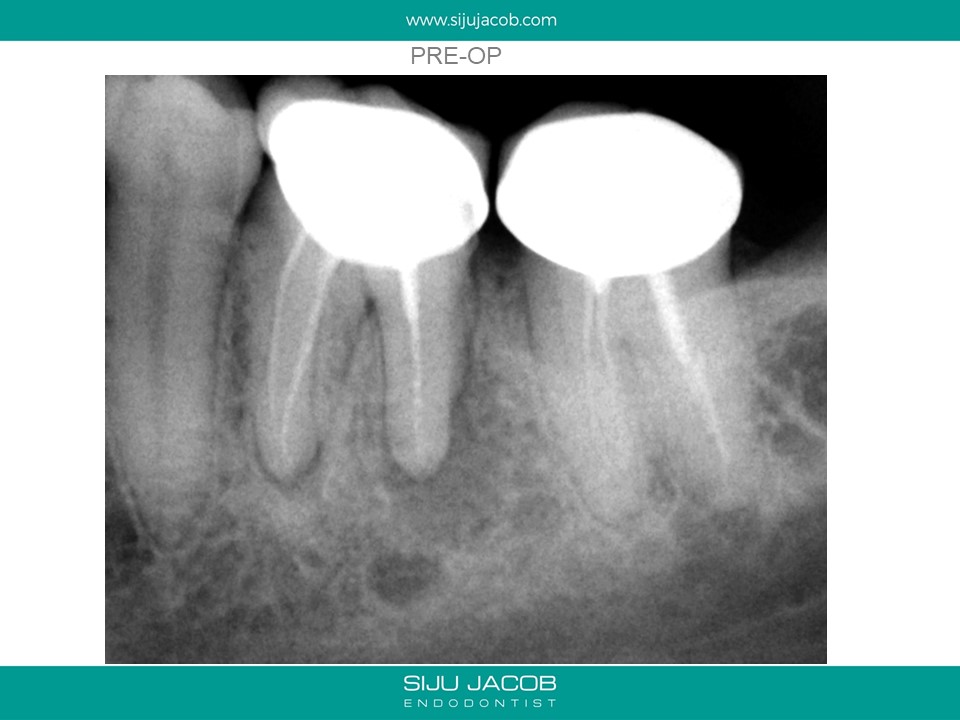

Written by Siju JacobApril 13, 2020 Molar Re-treat with large lesion This patient came with an acute abscess. Disassembly and re-treat with long term Caoh. One year recall shows healing. Share this: Share on X (Opens in new window) X Share on Facebook (Opens in new window) Facebook Like Loading... Related Leave a comment Cancel reply Δ